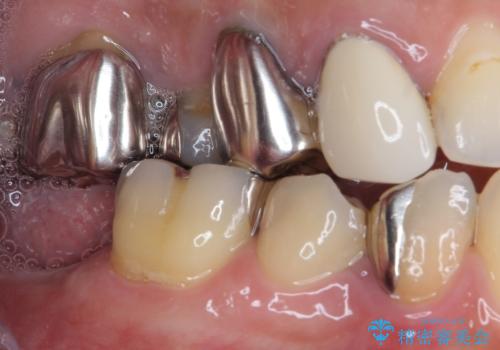

- 下顎左右の奥歯を治療途中で放置してしまっているとのことで来院された患者様です。

欠損部はインプラントによる補綴治療を、土台の外れてしまった歯は、根管治療を行った上で、補綴治療を行うこととしました。

骨格的に下顎が大きく上顎が小さいため、奥歯に力の負担のかかりやすい咬み合わせであるので、治療後は睡眠時にマウスピースを装着することで、セラミッククラウンやインプラント、治療をしたご自身の歯が長持ちするよう指導しています。